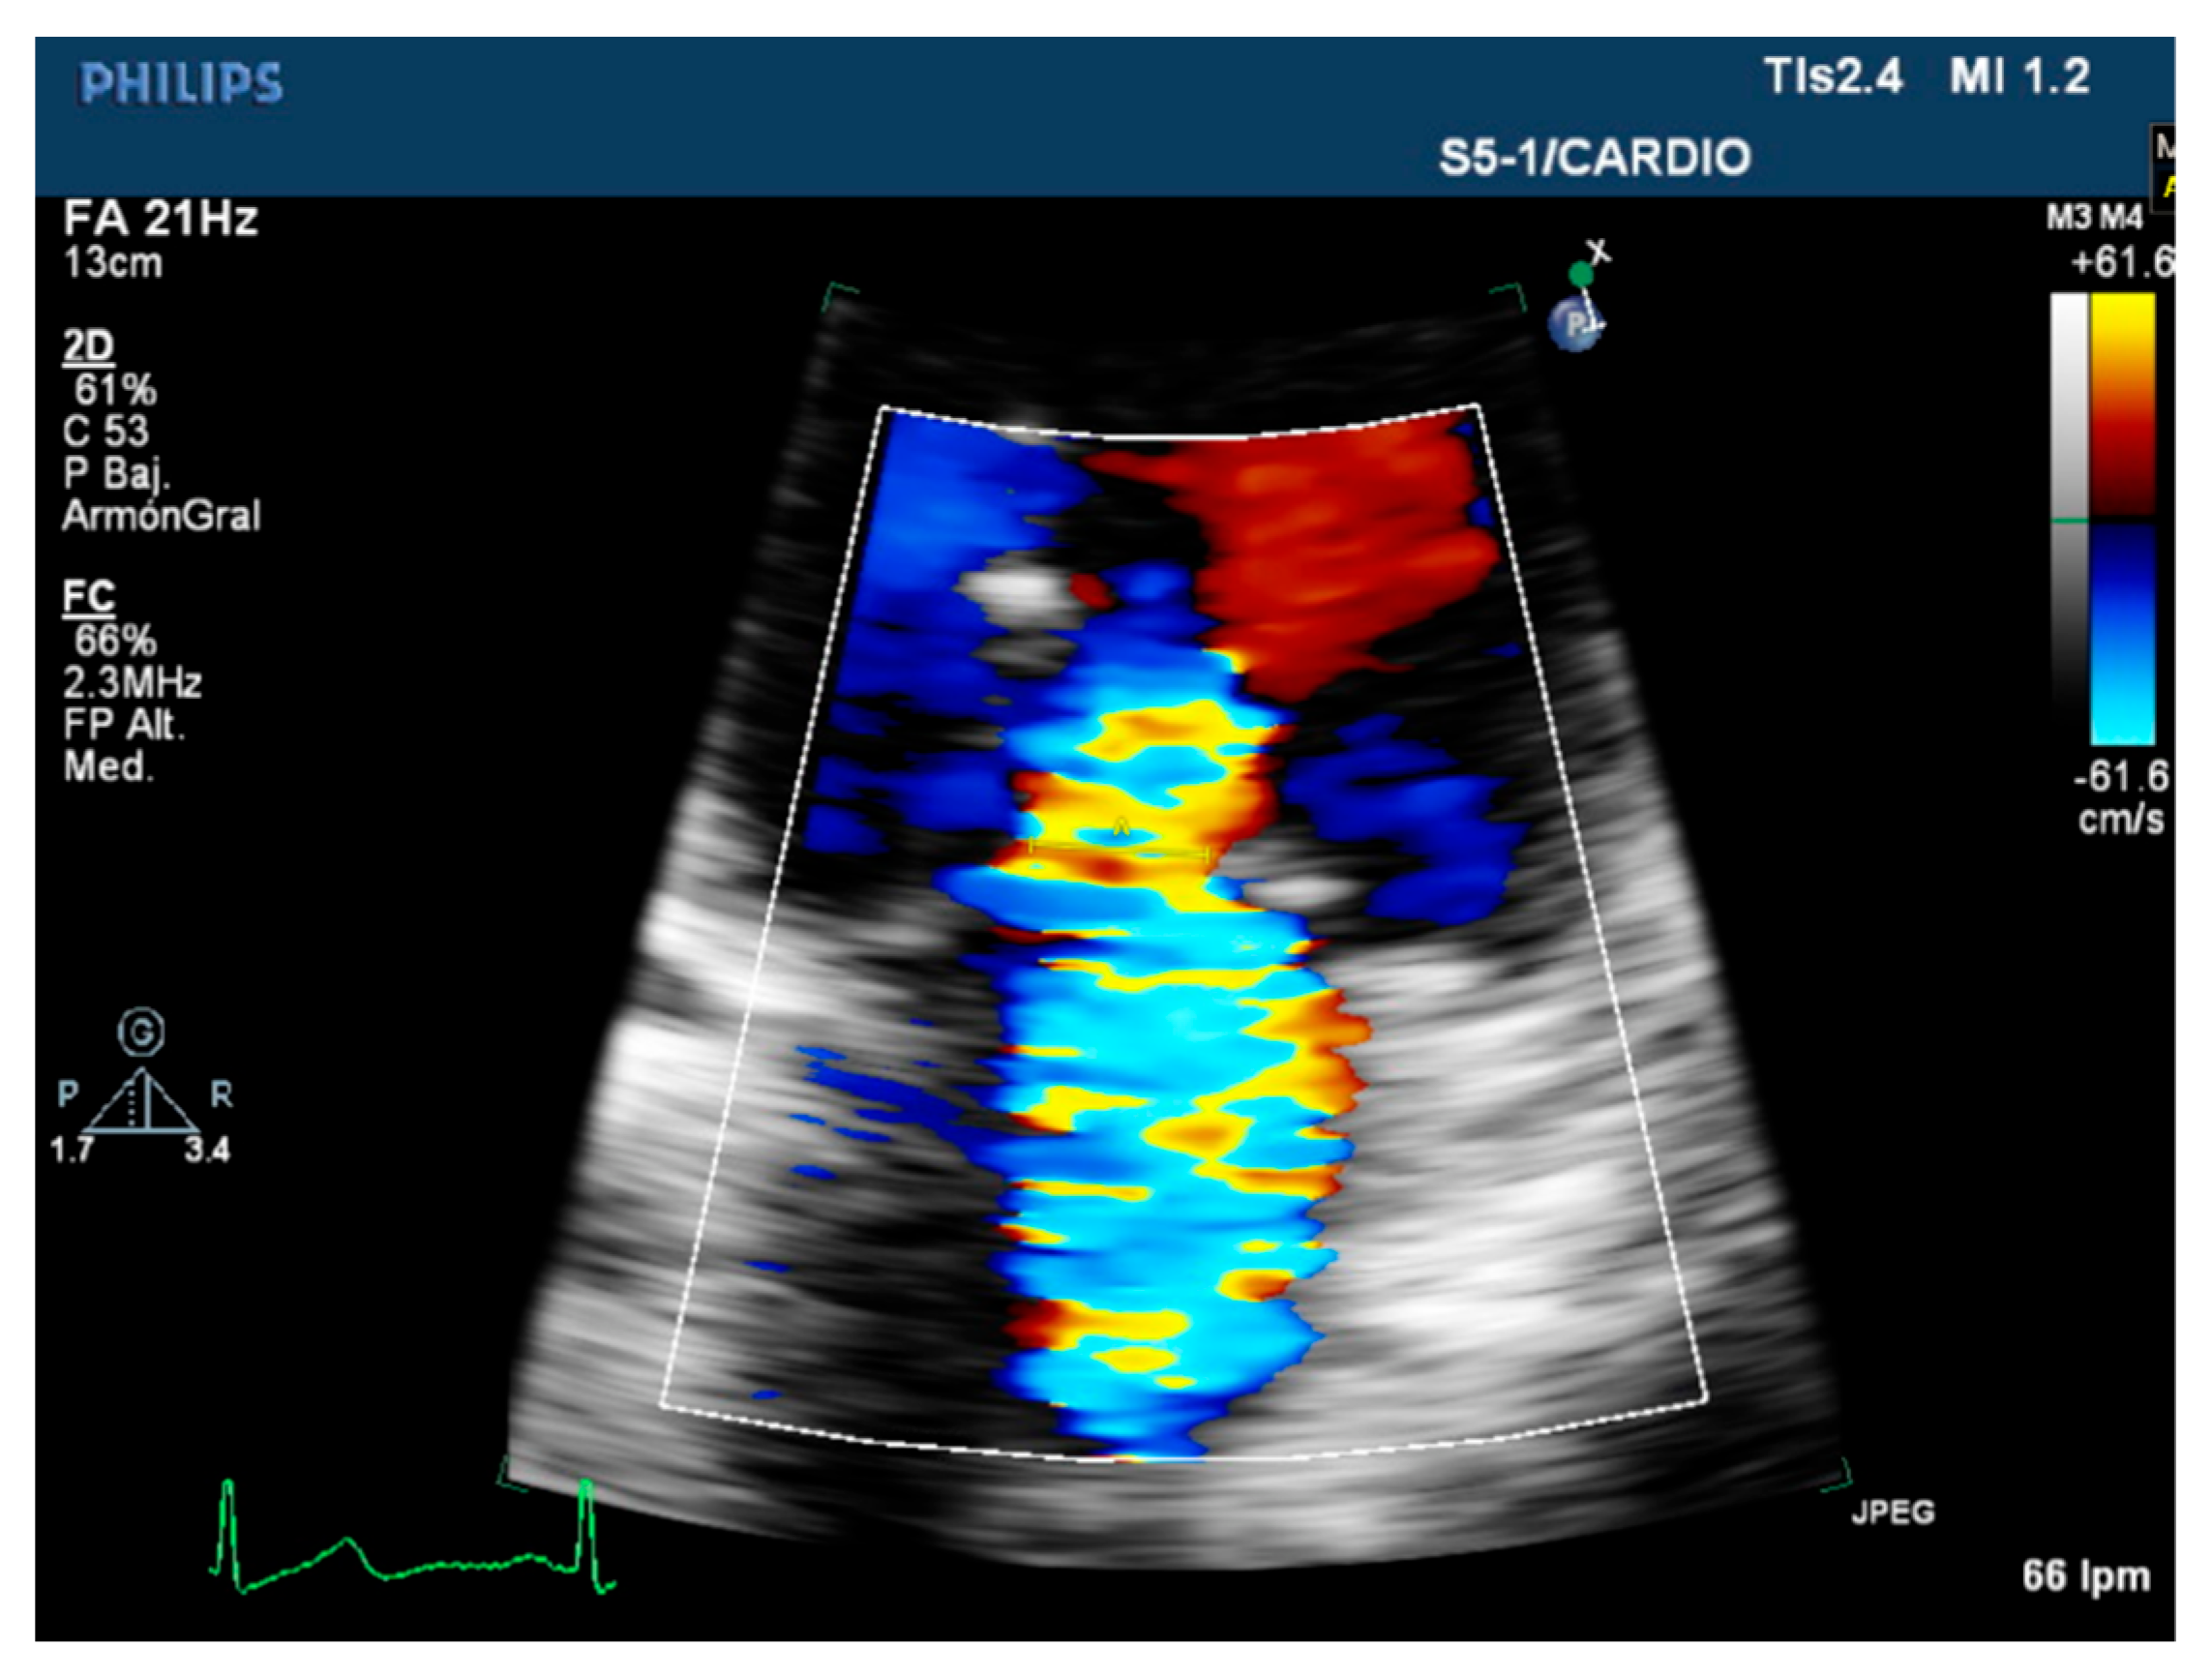

| Color flow jet | Qualitative. | Small, central. | Large central jet or eccentric reaching the posterior LA wall. |